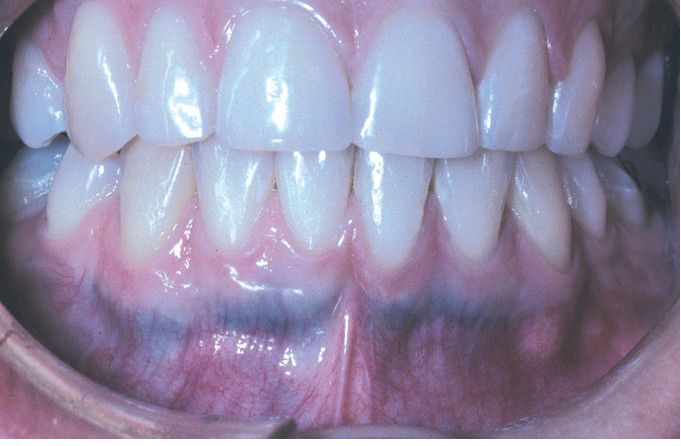

Minocycline-related Discoloration

. Blue-gray discoloration of the facial surface of the anterior mandibular alveolus because stained alveolar bone is visible through the thin mucosa